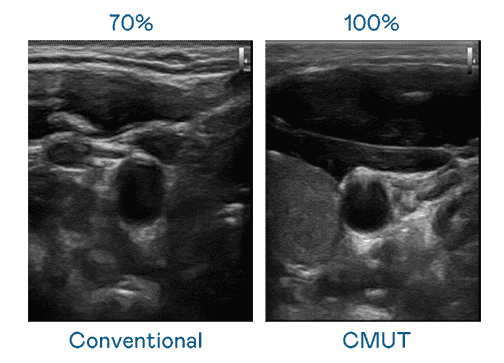

CMUT 技术是一种用电容式微机电元件来产生超音波讯号的技术。。与传统 PZT 压电式技术相比,,,,CMUT 频宽增加 30%,,,,更宽频的超音波讯号让影像解析度大幅提升,,,是实现高影像品质医疗超音波扫描、、、、促进精准医疗发展的关键技术。。。。

大频宽带来超清晰影像

超音波影像的解析度高低,,,首先取决于探头能发出的讯号频宽。。。。森林舞会 CMUT 可提供高清晰的超音波讯号,,,,提供高频宽、、、、高灵敏度、、、、影像纹理细节更高的超音波影像,,,协助医护人员缩短影像判读时间及利用精准的医疗影像进行诊断。。。